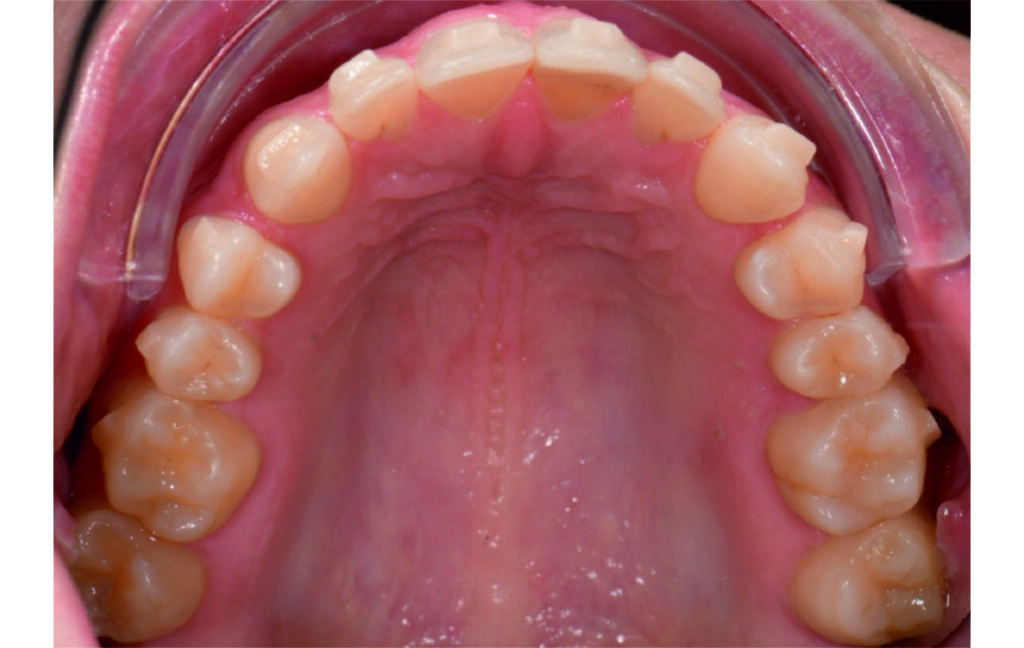

Angle Class II 2mm on the right, Angle Class II 2mm on the left, light mandibular asymmetry to the right, lower central line 1mm to the right, upper central line 1,5mm to the left, 1mm overjet and overbite. Sagittal asymmetry of upper dental arch. Light crowding upper and lower frontal segments, severe attrition of posterior teeth, night bruxism. Normal sagittal position of both jaws, high angle case, steep mandibular ramus,excessive lower facial height, open bite tendency.

The case initially presented as a moderate Class II on the right and a Class II tendency on the left, with tapered dental arches and an anterior open bite extending to tooth 26 in segment II.

A 1.5 mm deviation of the upper dental midline to the patient’s left was noted, along with a slight mandibular midline shift to the right, likely due to asymmetrical mandibular growth observed in the facial structure. Severe mesial rotations of teeth 16 and 26 were evident in the initial records. As derotation of 16, 26, 17, and 27 progressed up to aligner 16, the premolars in segments I and II moved distally, resulting in a bilateral Class I relationship, as intended in the initial treatment plan.